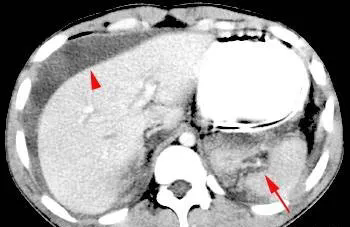

(上图为脾撕裂伤3级,红箭头所指为活动性出血。)

Ⅲ级:撕裂伸展至脾门及脾实质内,血肿直径>3 cm;